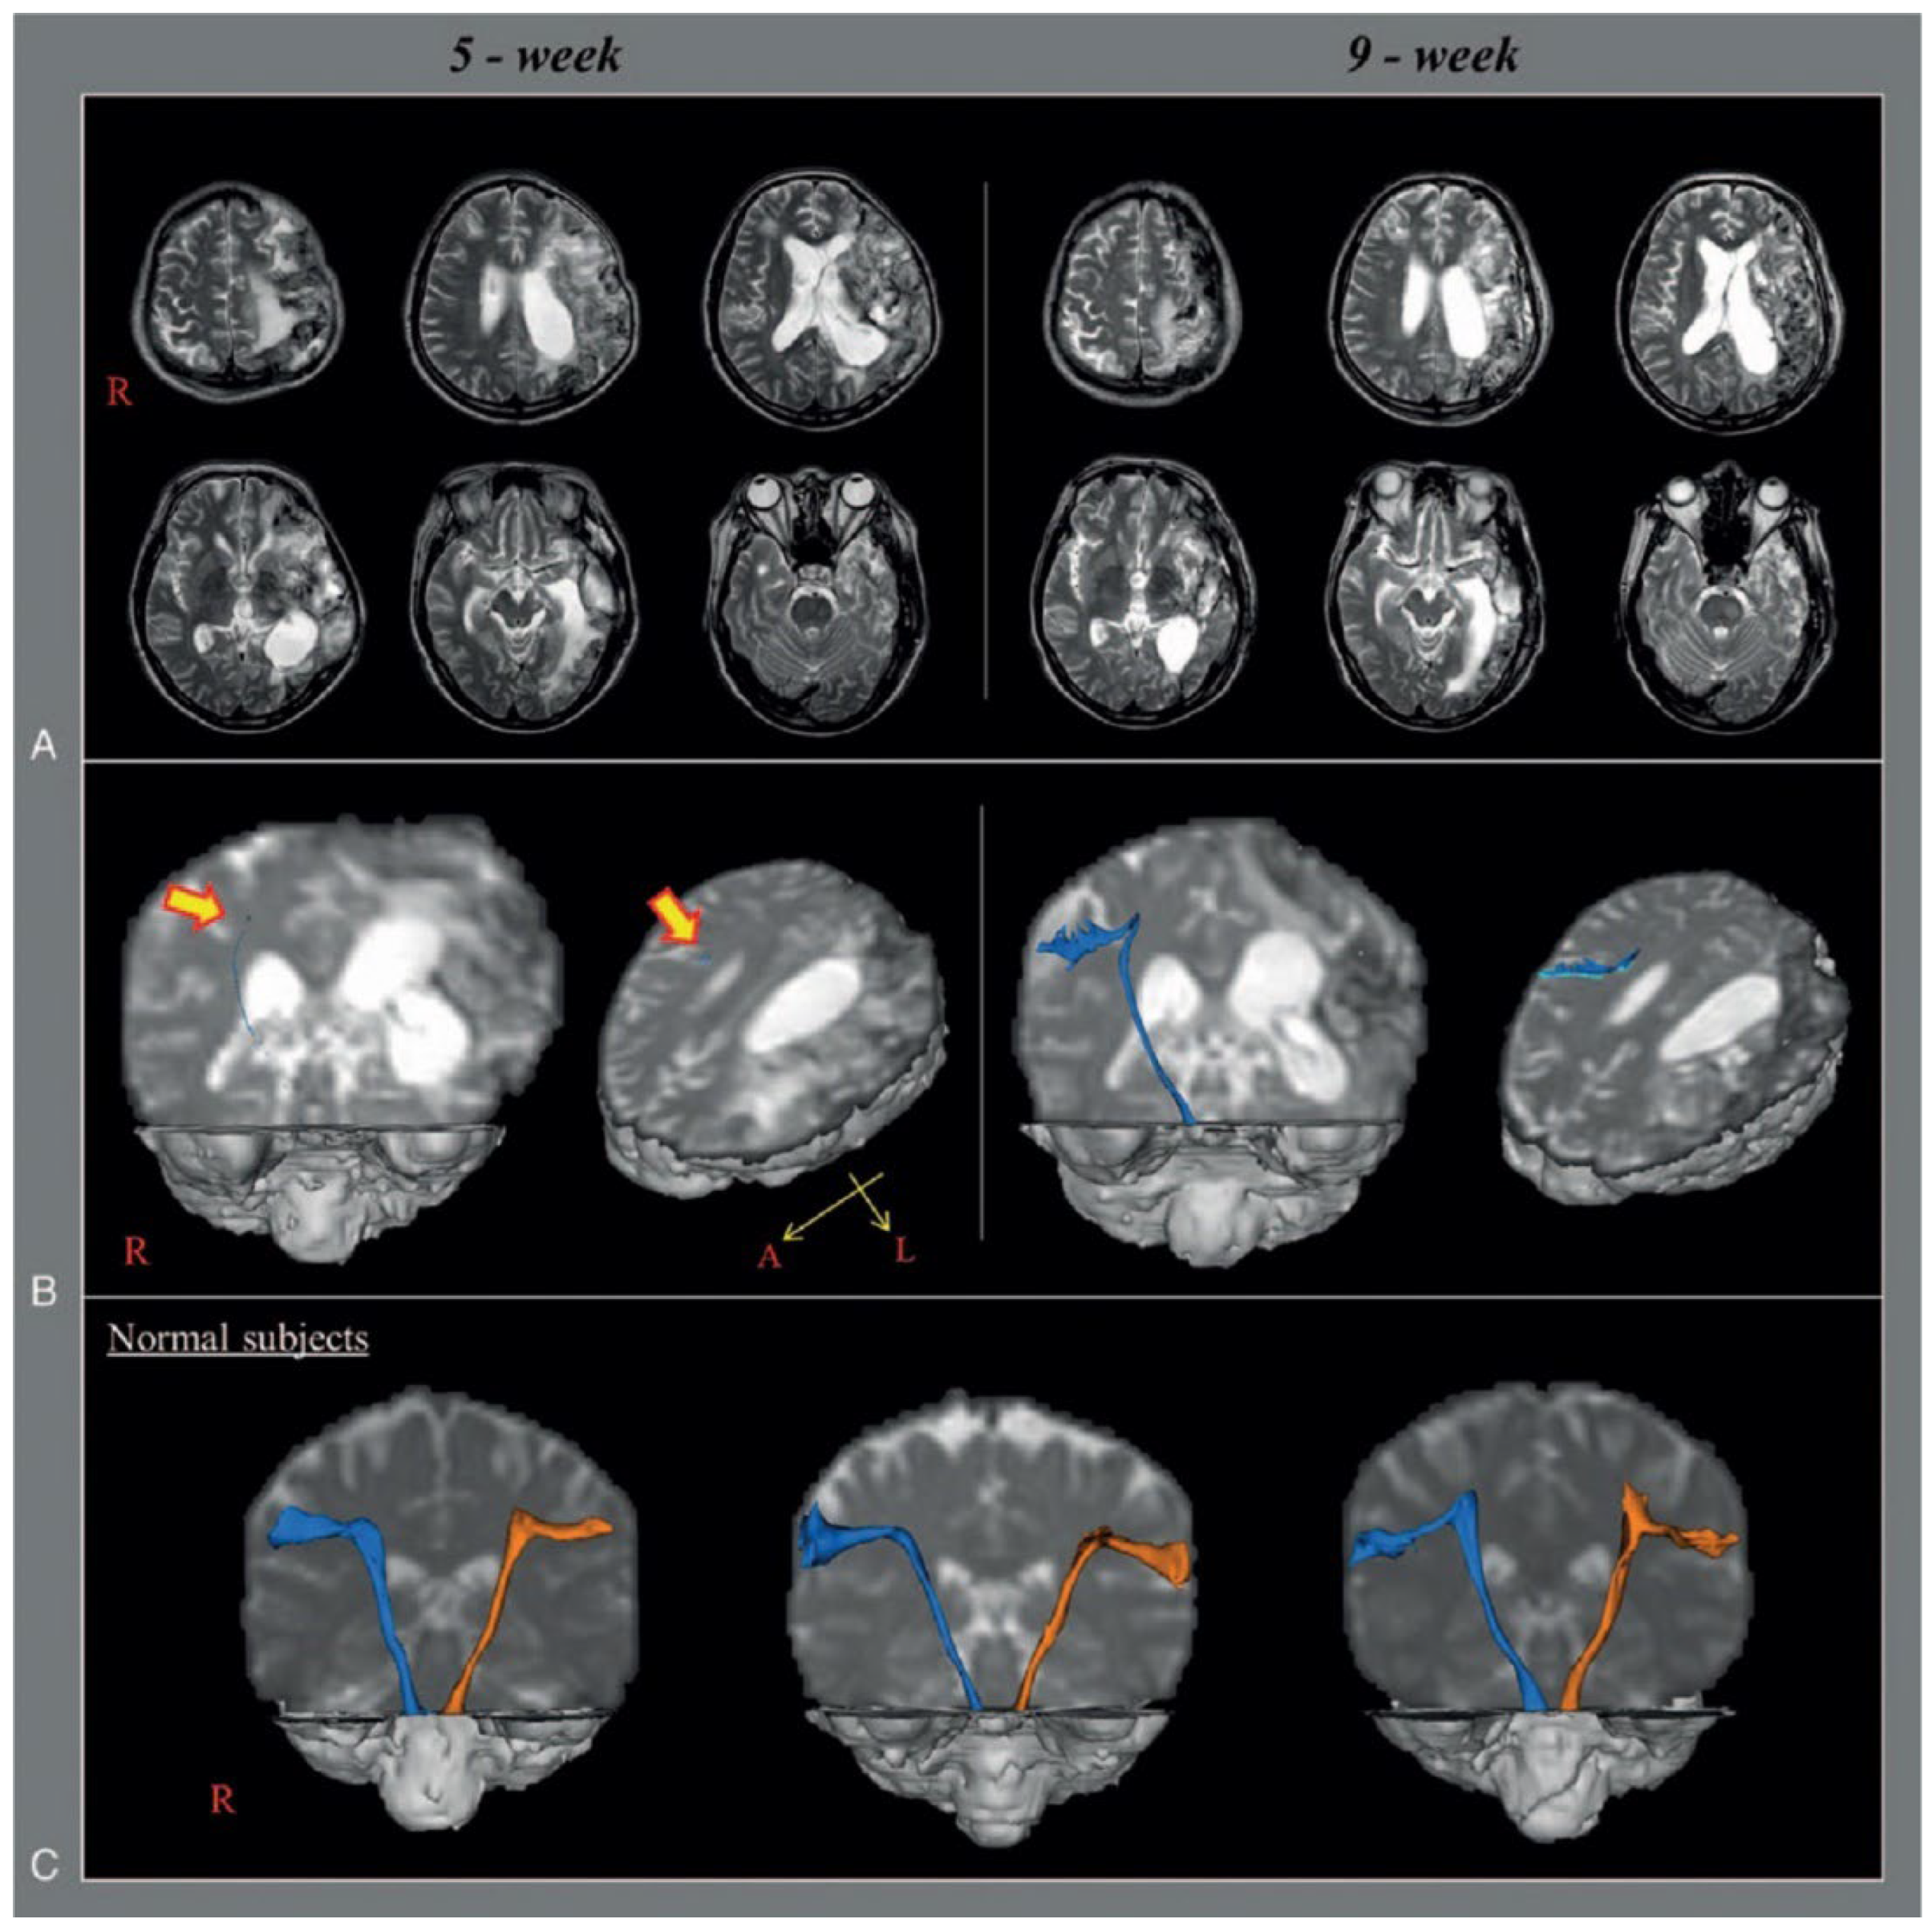

Jang et al. (2017) studied the neural tract causing dysphagia in a stroke patient (n = 1, 59 years old, male, left middle cerebral artery infarction) using diffusion tensor tractography [33]. The study subject was wearing a Levin tube due to severe dysphagia after a stroke [33] (Figure 3). DTT was performed at 5 and 9 weeks post stroke, and the results were compared to those of normal individuals of the same gender and age (control group, n = 3). The DTT results at week 5 revealed that the left CBT was not analyzed due to severe damage, and the right CBT was only marginally analyzed due to severe narrowing at the subcortical white matter level. However, the patient showed improvement in dysphagia at week 9, so the Levin tube was removed, and the patient started to eat normally. In addition, the DTT at week 9 showed that the left CBT had not been reconstructed in the same way as it was at week 5, but the right CBT was smoothly reconstructed, extending into the cerebral cortex. Thus, CBT is significantly involved in the pathogenesis of dysphagia; particularly, the recovery of the right CBT is associated with the recovery of dysphagia symptoms, even though the left CBT was not reconstructed. Limitations of this study include the potential for false-negative results due to crossing fibers and partial volume effects imaged using DTT. Second, although the reconstruction of CBT was identified, the parameters of DTT, such as fractional anisotropy, tract volume, and mean diffusivity, were not specified. Finally, the mechanism by which dysphagia improved after restoration of unilateral CBT was not explained.

Figure 3.

Anatomical structure of CBT captured using DTT [33]. (A) T2-weighted brain magnetic resonance (MR) images at 5 and 9 weeks after onset show leukomalactic lesions in left middle cerebral artery territory. (B) Diffusion tensor tractography (DTT) for the corticobulbar tract (CBT). On 5-week DTT, the right CBT is discontinued at the subcortical white matter and shows severe narrowing compared with those of normal subjects, whereas the left CBT is not reconstructed. By contrast, on 9-week DTT, the right CBT is extended to the cerebral cortex with thickening, whereas the left CBT is still not reconstructed. (C) Reconstructed CBT of normal subjects (55-year-old man, 57-year-old man, and 60-year-old man), blue arrow: right CBT, orange arrow: left CBT. Copyright by Jang et al. (2017) [33].